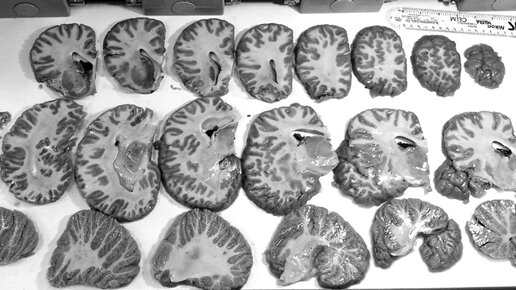

Эволюция нервной системы.